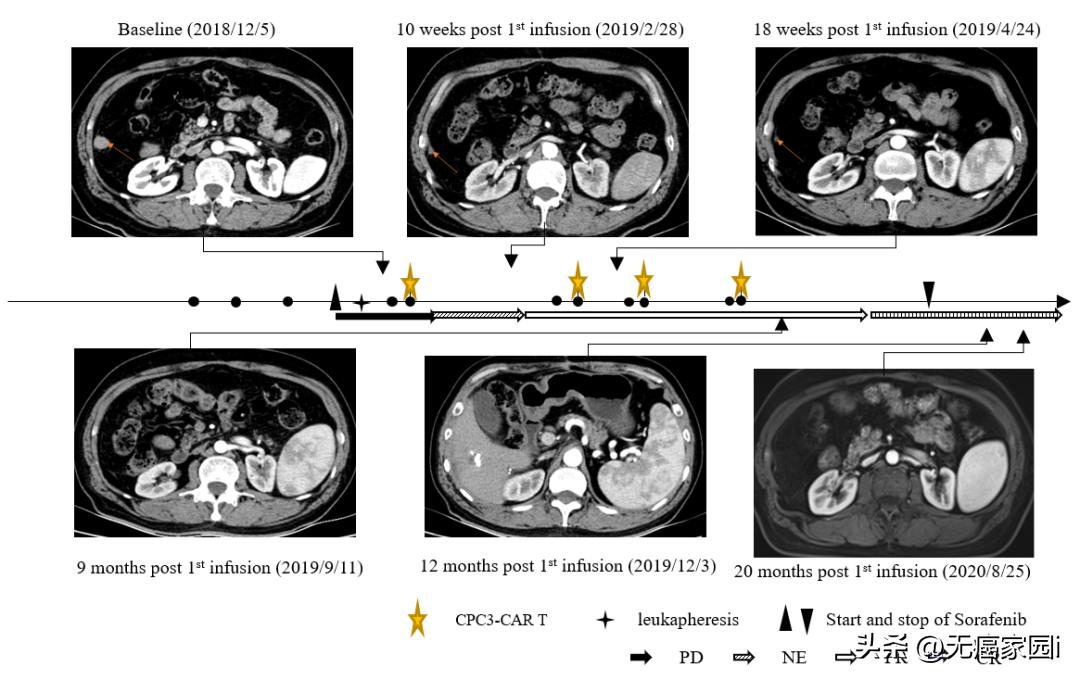

该研究团队是最早报道了GPC3是CAR-T治疗的理想靶点,且率先开展CAR-T治疗肝细胞癌的临床试验。此项研究报道了 1名晚期肝细胞癌患者在接受GPC3 CAR-T细胞与索拉非尼联合治疗后获得了完全缓解(CR)和长期生存。

这是一名患有乙型肝炎病毒(HBV)相关肝细胞癌的60岁男性,于2018年5月接受手术,2018年8月术后发生肝癌复发并出现肺转移,随后又进行了经动脉化疗栓塞治疗(TACE)处理肝部病灶和介入消融处理肺部转移。不幸的是,在2018年11月6日出现疾病进展,有幸符合临床试验入组条件。在入组后,该名患者接受单采制备GPC3 CAR-T细胞。在单采后7天,患者开始服用索拉非尼,400mg/次,2次/d。患者接受了4个周期的GPC3 CAR-T细胞(CT011)治疗,每个周期分为两次输注。在接受CT011治疗的每个周期之前,进行清淋化疗预处理。共输注4×109 个GPC3 CAR-T细胞。

CT011联合索拉非尼治疗耐受性良好。 患者从第3个月开始达到部分缓解(PR), 并 在第一个 CT011 输注周期后的第12个月达到完全缓解 。 肿瘤超过36个月没有进展,在第一次输注后保持完全缓解状态超过24个月。

据悉,这是CAR-T细胞与酪氨酸激酶*制剂抑**联合治疗后报告的首个完全缓解病例。临床结果表明, GPC3 CAR-T细胞与索拉非尼的联合治疗,可能成为治疗GPC3表达阳性的晚期肝细胞癌患者的一种有前景的疗法。